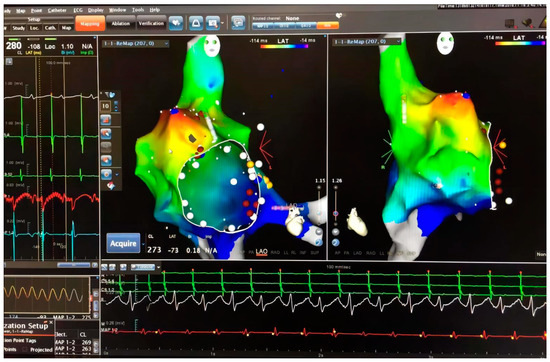

The patient was sent to the operating room immediately. Three-dimensional mapping guiding by EnsiteTM system was performed with zero-fluoroscopy, which also confirmed the same origin. (Figure 3). To avoid surgery, low-power, short-course ablation was performed again, and the results remained ineffective. Attempts to convert atrial fibrillation and terminate tachycardia by high-frequency stimulation also failed. Based on the failure of these attempts, surgical removal of the appendage became inevitable.

Figure 3. Electrophysiology study was performed again with zero-fluoroscopy approach guided EnsiteTM system. With the high-density mapping, the originating point was confirmed in the apex of the right atrial appendage.